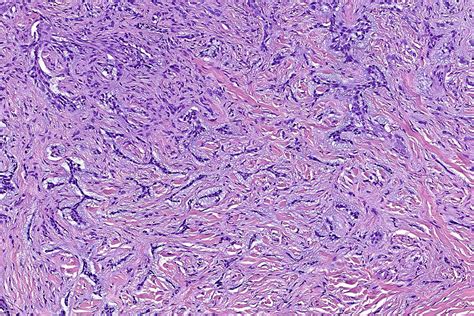

Nodular Basocellular Carcinoma

Basal cell carcinoma (BCC) is a type of skin cancer that begins in the basal cells—a type of cell within the skin that produces new skin cells as old ones die off. Nodular Basocellular Carcinoma is the most common subtype of this cancer, accounting for approximately 50% to 80% of all BCC cases. It typically presents as a small, raised, pearly, or translucent nodule that may have visible blood vessels (telangiectasia) on its surface.

Because these lesions often occur on sun-exposed areas of the body, such as the face, ears, neck, and scalp, they are highly visible. Over time, the center of the nodule may become depressed, or it might ulcerate and crust over, which is a hallmark sign that prompts many patients to seek medical advice.